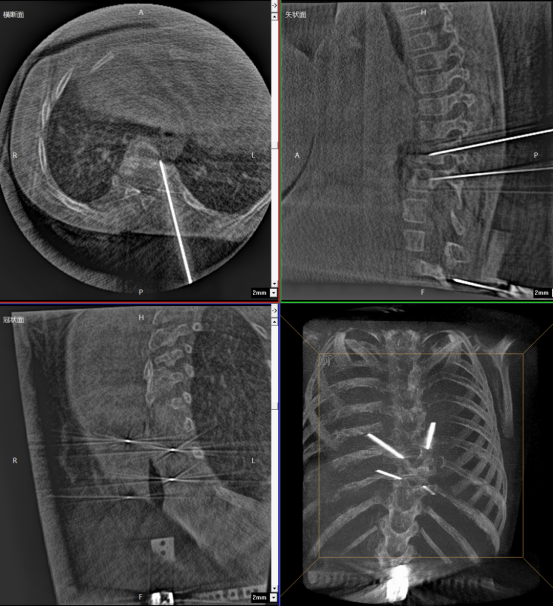

One-time planning for quadruple K-wire insertion

The robotic arm enhanced stabilization of surgical instruments, enabling precise execution. Guided by pre-planned trajectories, the system achieved accurate single-attempt pedicle screw placement within narrow vertebral pedicles - effectively navigating the 'anatomical labyrinth'. This approach eliminated risks associated with repeated positioning attempts. The fully integrated system demonstrated perfect coordination, successfully completing the implantation of four pedicle screws with sub-millimeter accuracy.

Fluoro-verified precise K-wire insertion